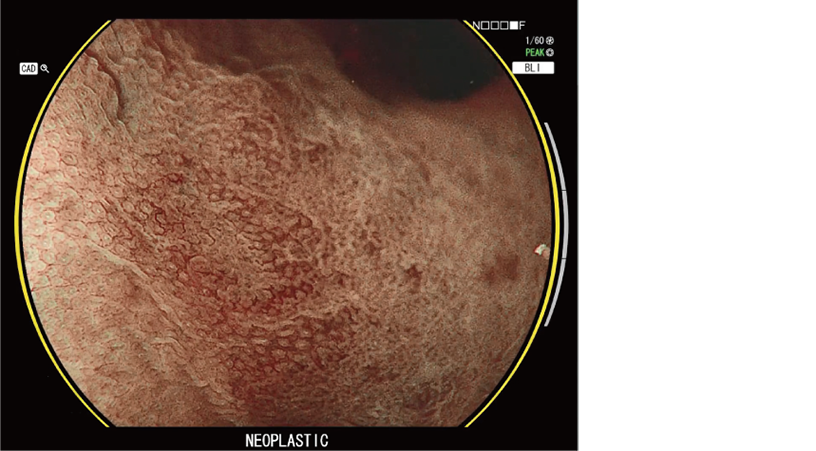

CAD EYE is FUJIFILM's brand name of computer-aided diagnosis (CAD) function for endoscopy. CAD EYE has been developed utilizing AI deep learning technology with an immense amount of clinical images.

Characterization